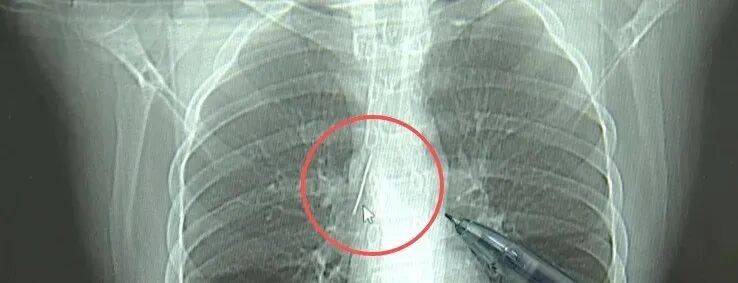

近日,安徽17岁小伙小陆参加征兵体检,胸片结果显示:胸腔内有一处金属高密度影,形态细长,像一根针。

进一步的CT检查确认,异物是一枚金属针,斜插在肺组织内,位置十分凶险。

杭州市第一人民医院心胸外科副主任冯兴说:“我们看到这个针的尖锐部,正好指向他体内的一个大血管,边上是上腔静脉和胸主动脉,因此这个针稍有不慎,就有可能造成周边血管的损伤,甚至危及生命。”

医生推测,那枚针很可能就是在那时候扎入体内的。针在小陆体内滞留了十几年,既没有引发感染,也没有造成气胸,堪称医学奇迹。上周四,医院为小陆实施了mini单孔胸腔镜微创手术,切口仅两厘米左右,成功将针完整取出。